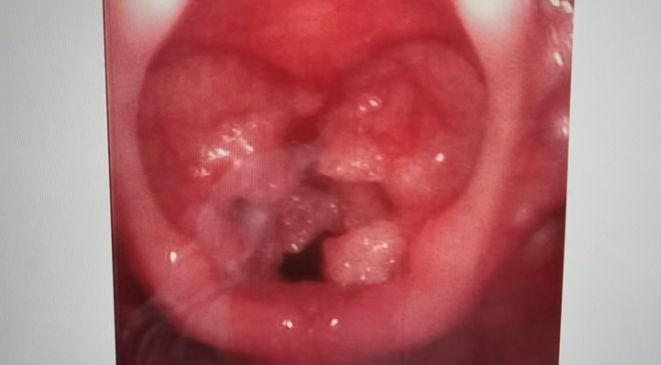

Bác sĩ kiểm tra thì phát hiện có cục u đỏ hình dáng giống súp lơ mọc trong cổ họng của Quả Quả. Khối có màu đỏ và bề mặt không bằng phẳng xác định là u nhú thanh quản do nhiễm virus HPV. Hơn nữa, khối u đã rất lớn, chiếm một khoảng không gian đáng kể trong cổ họng, khiến giọng nói của bé trai trở nên khàn khàn.

| U nhú trong cổ họng của Quả Quả. |

Bác sĩ cho biết, khối u tương đối lớn, nếu không phẫu thuật, khối u ngày càng lớn sẽ càng dẫn đến khó thở, ảnh hưởng trực tiếp đến quá trình sinh trưởng và phát triển của Quả Quả. Gia đình đồng ý phẫu thuật và hiện tại, bé hồi phục dần.